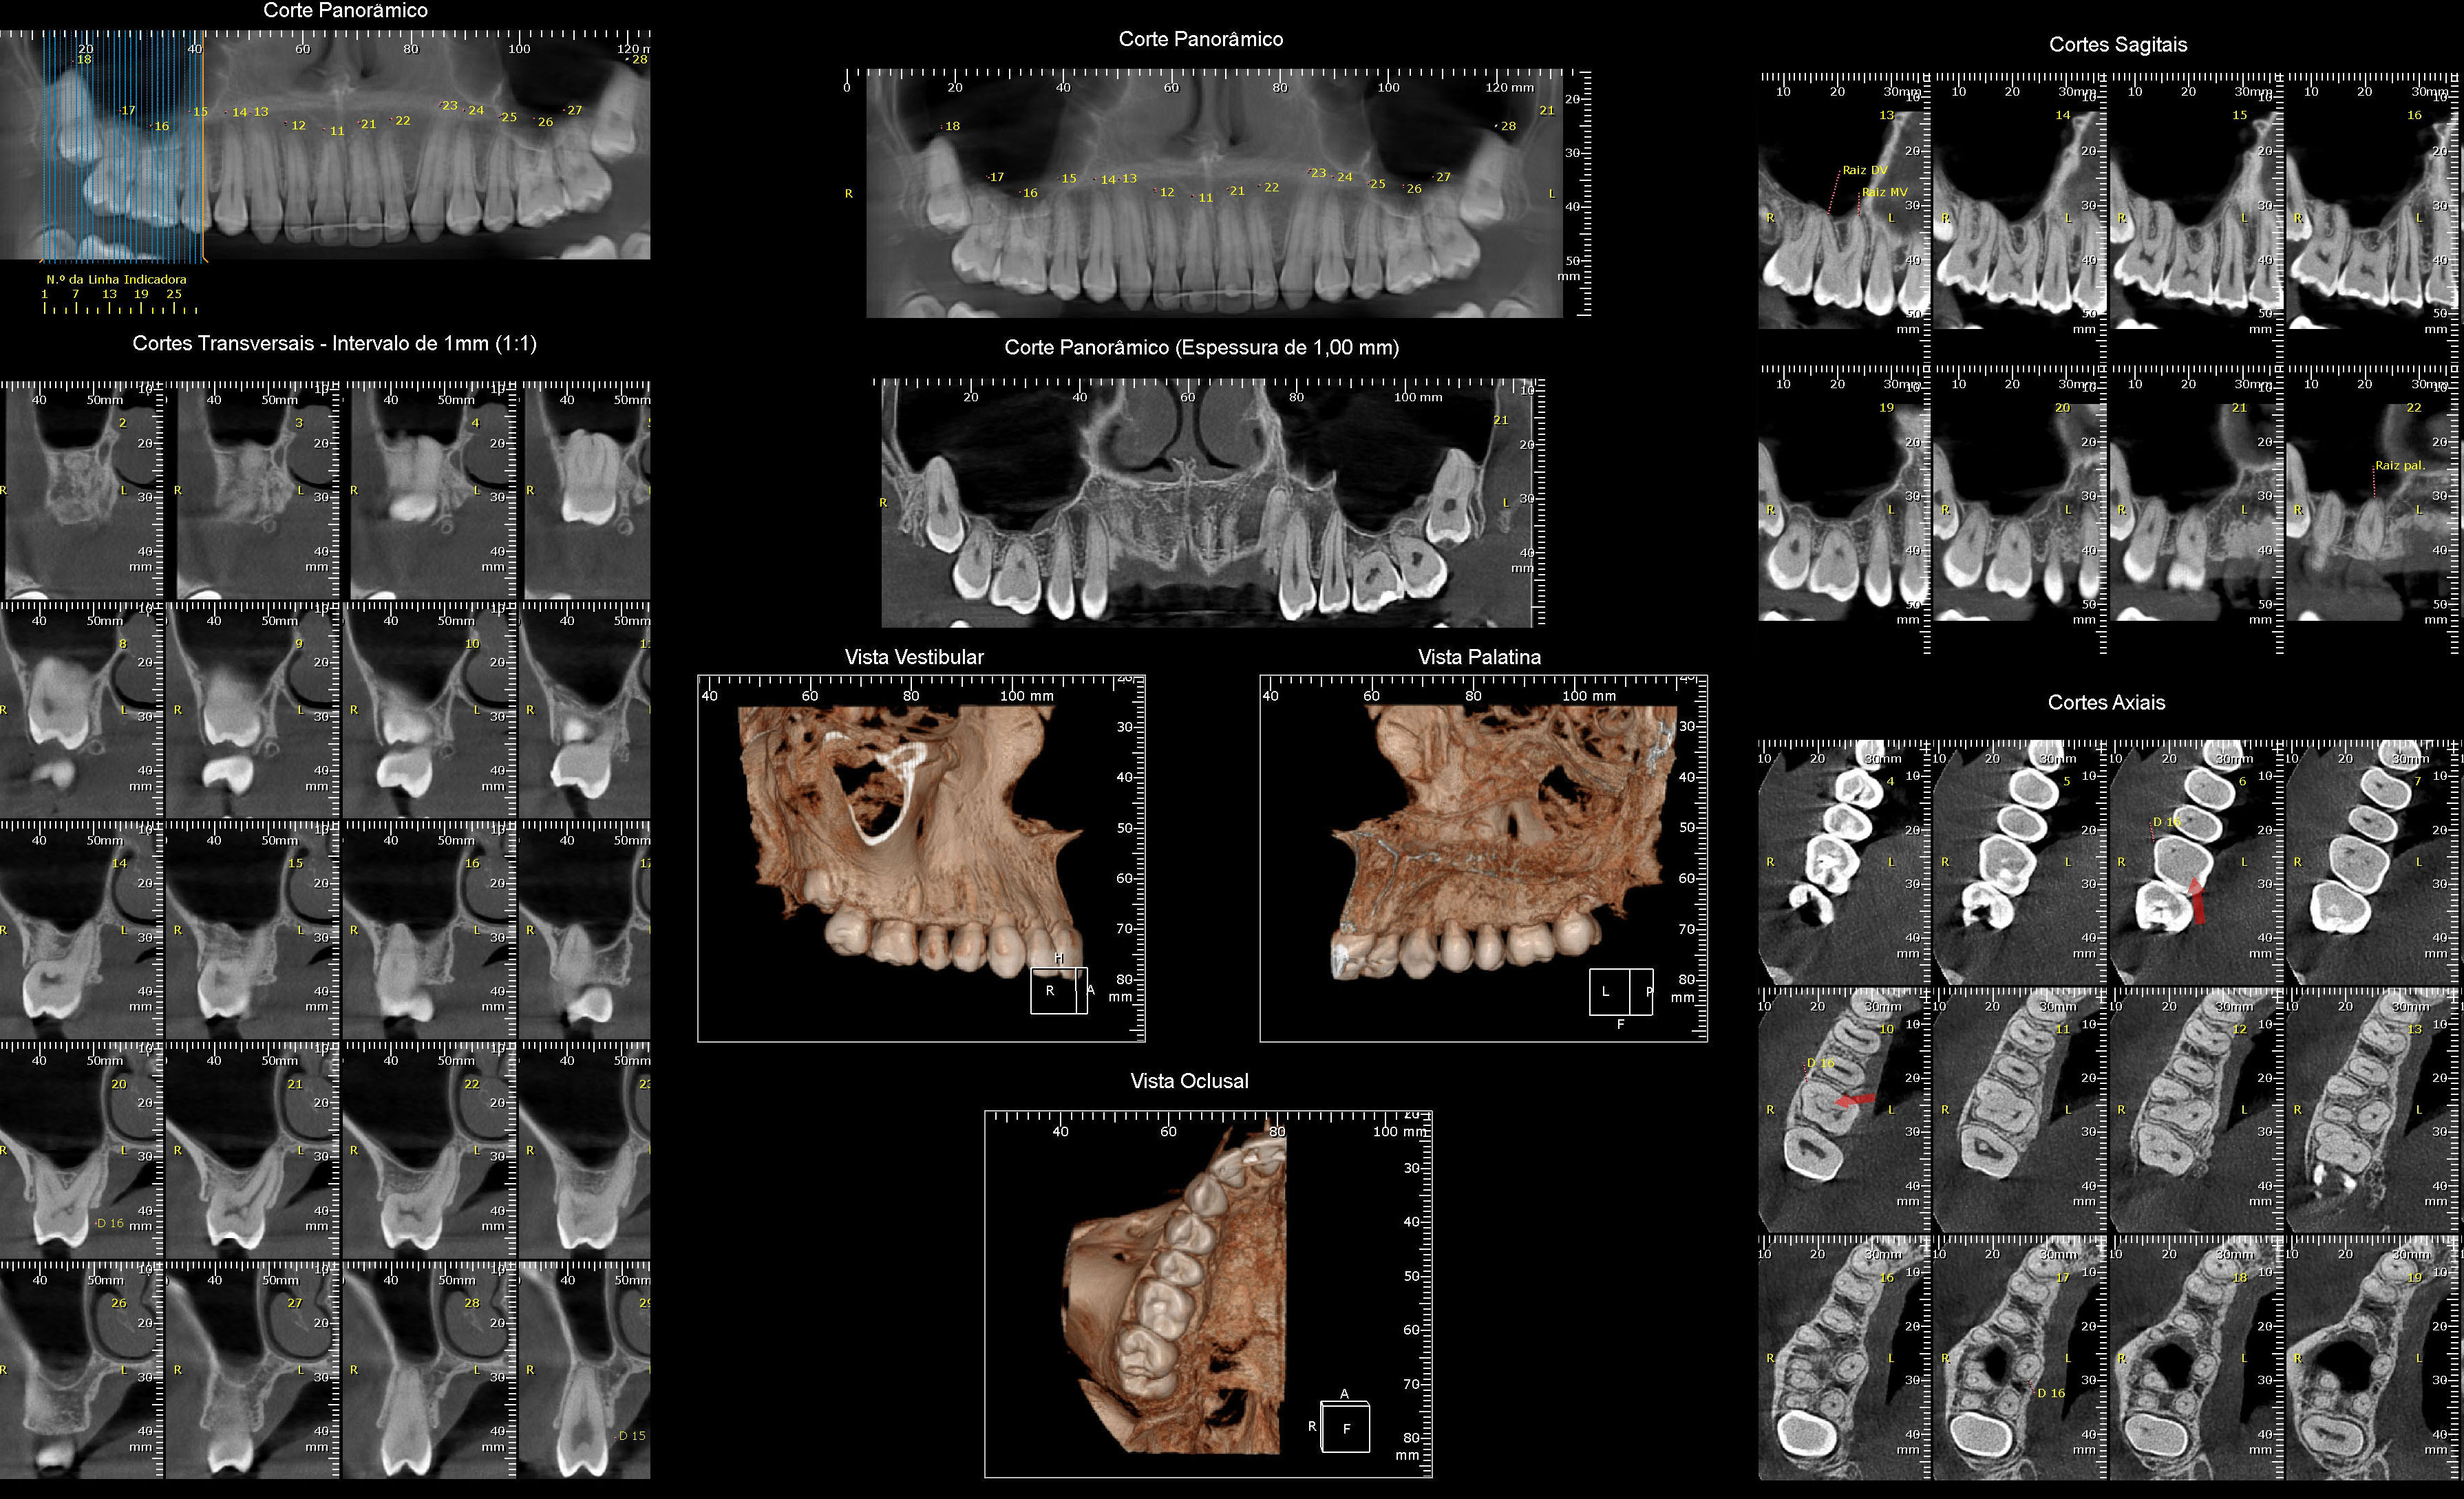

Tomografia Computadorizada

- Exame Tridimensional dos Maxilares

- Tomógrafo de Altíssima Resolução